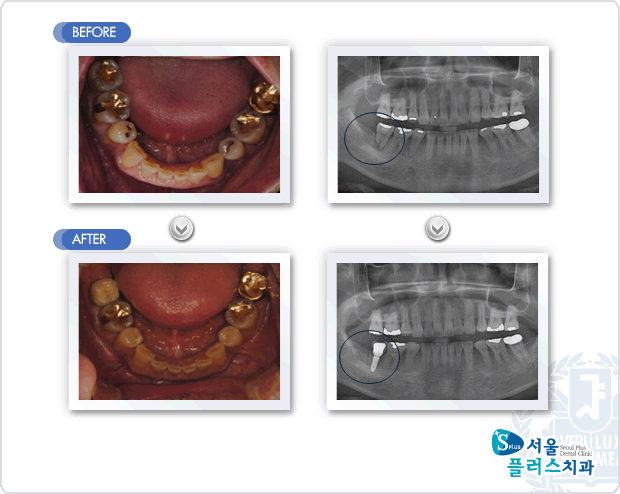

[임플란트] 하악 우측 제2대구치의 오래된 염증